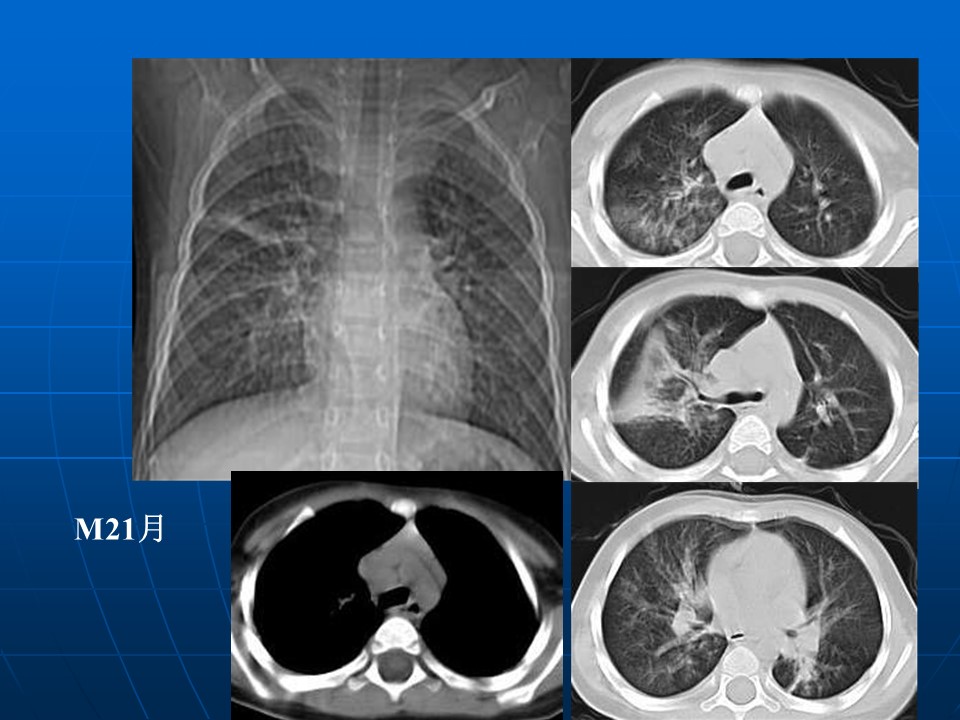

【PPT】早期肺癌易漏诊征象分析